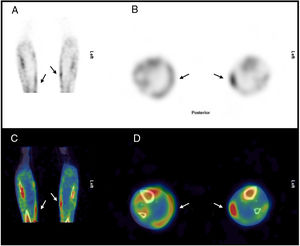

En el estudio planar con difosfonatos no se apreciaron hallazgos gammagráficos significativos en la fase vascular, mientras que, en la fase ósea, se observó una discreta captación del radiotrazador en regiones mediales de las piernas (fig. 1). Este hallazgo fue confirmado por la tomografía computarizada de emisión monofotónica (SPECT), tomografía computarizada de emisión monofotónica/tomografía computarizada (SPECT/TC) (fig. 2) e imagen de reconstrucción 3D (fig. 3), donde se evidenciaron depósitos focales del trazador en partes blandas, en relación con la localización de las lesiones ulcerosas más mediales, confirmando el diagnóstico de calcifilaxis.

La biopsia cutánea mostró calcificaciones de vasos de mediano calibre en la dermis e hipodermis y calcificaciones perineurales (fig. 4). Estos hallazgos eran compatibles con el diagnóstico de calcifilaxis.